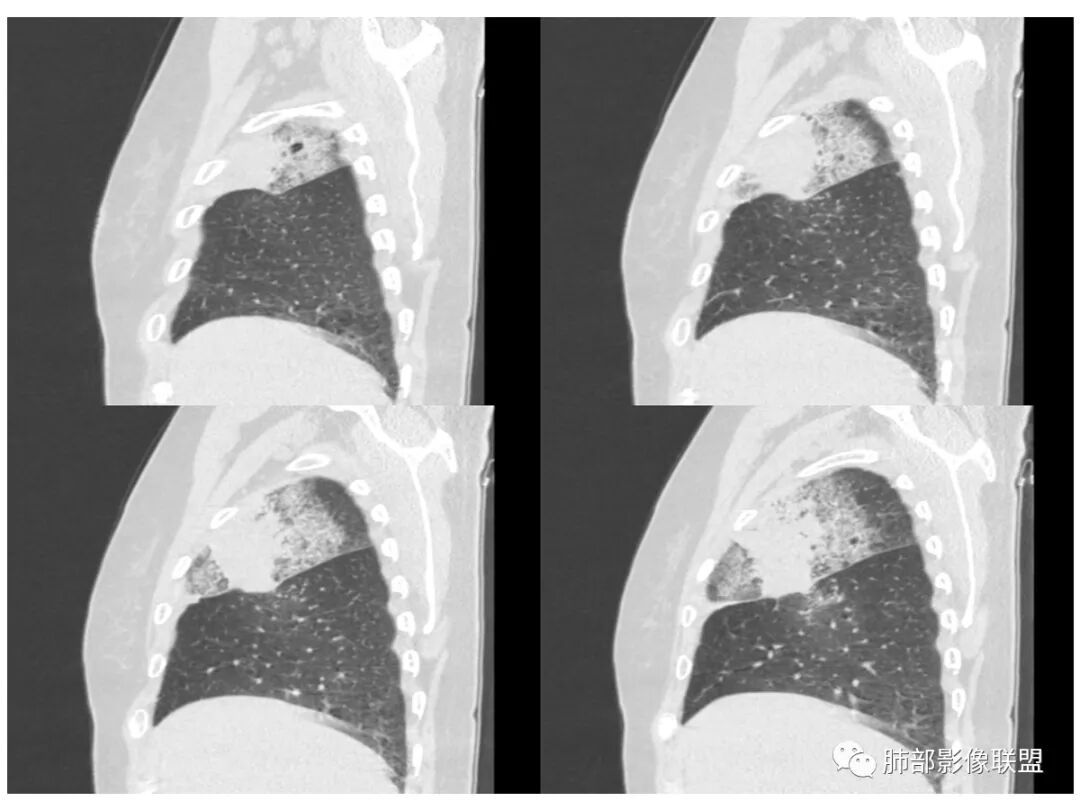

胸CT:右肺上叶实变内可见支气管充气征,近端支气管狭窄,远端扩张,周围可见毛玻璃影,右肺中叶支气管闭塞,并可见气道壁钙化,右肺中叶体积缩小,实变内可见空洞,并可见气液平面,空洞周围可见毛玻璃样影,右肺下叶支气管开口狭窄,右肺门淋巴结肿大。纵隔窗可见病灶与壁层胸膜间隙增宽,考虑良性病变-----感染性病变------TB?

老年女性,慢性病程,咳嗽伴白色粘液痰,无发热腹痛,糖尿病,白细胞及C反应蛋白不高,血沉快,铁蛋白高。胸部CT,右肺上叶大片状实变伴磨玻璃密度影,边界不清,边缘局部膨隆,叶裂弧形下坠,实变影宽基底与胸膜相贴;右肺下叶前基底段见类似病灶;右肺中叶不张并空洞形成,空洞内见气液平面;综合考虑右肺上叶及下叶肺炎型肺癌,右肺中叶结核。

老年女性,病史1月,右肺上中叶大片状影,跨叶,上叶为主,磨玻璃为主,边界模糊,部分实变,内见空洞影和液气平面,壁光滑,支气管开口狭窄,局部有扩张,右肺门淋巴结钙化,首先考虑感染性病变,结核可能,鉴别粘液腺癌。

老年女性,亚急性起病,右肺上中叶大片状影,跨叶,上叶为主,磨玻璃为主,边界模糊,部分实变,内见空洞影和液气平面,壁光滑,洞内可见结节形成,局部有扩张,首先考虑感染性病变,结核可能;洞内可见结节样病灶,鉴别合并曲霉、肿瘤。

患者老年女性,亚急性起病,胸部CT:右肺上叶大片实变,可内见坏死性空洞,可见mGGO,GGO边缘清晰,局部彭隆,内见支气管充气征,可惜没增强,粘液腺癌要考虑,但病灶明显是内朝外不支持,综合考虑结核,建议查痰找抗酸杆菌、气管镜

2.南大理论:粘液腺癌起源于外周,所以主体病灶位于胸膜下多见,这个病人主体病灶位于中心,外周磨玻璃为主,部分磨玻璃模糊

3.熊老师告诉我们:肺结核可以有磨玻璃,这个我以前一直不知道,右肺门淋巴结有钙化,病灶内纵膈窗隐约细细点状钙化,所以结核磨玻璃可以,